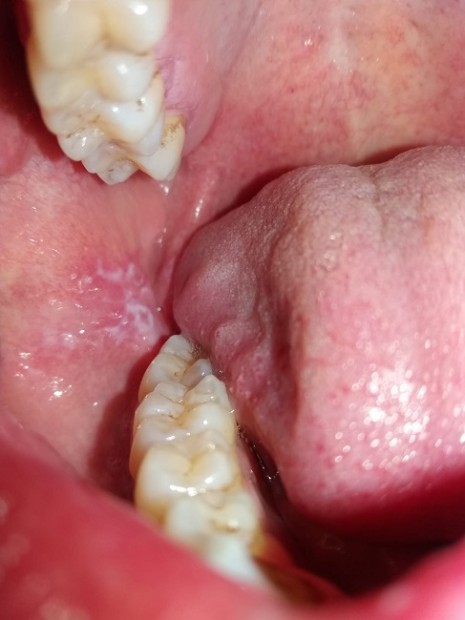

Fig. 12. Leukoplakia